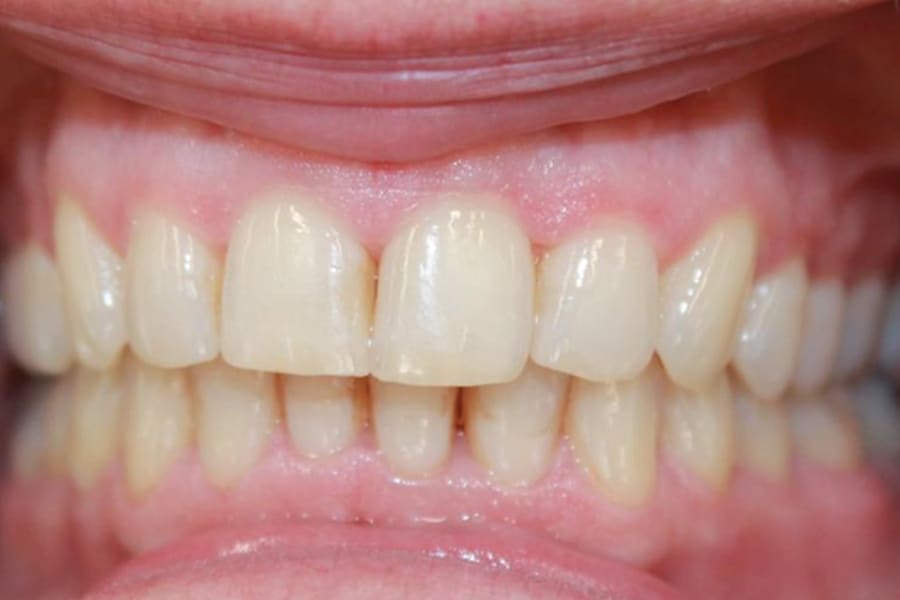

A 54-year-old woman presented with a chief complaint of teeth crowding. After comprehensive digital records were obtained, ClearCorrect® aligner therapy (Straumann, clearcorrect.com) was chosen with an anticipated 12-month treatment duration. The patient exhibited moderate anterior crowding, a class II molar relationship, and narrow arches. The treatment plan aimed to resolve the class II discrepancy, expand the arches, and establish proper anterior alignment. A total of 25 active aligners plus two retention aligners were prescribed. Attachments were selectively placed on the maxillary and mandibular canines to premolars, minimizing bulk while maintaining control over torque and posterior alignment. The patient was instructed to wear class II elastics full-time, which was crucial to achieving molar correction and arch expansion. Her outstanding compliance with class II elastics contributed to a significant improvement in molar position and transverse arch development. After completing the active phase, the patient transitioned to retainers to ensure long-term stability of the results. Given the patient’s initial class II occlusion, monitoring retention was emphasized to prevent relapse. The patient was extremely pleased with the outcome, demonstrating a broadened smile and improved occlusal function. This case underscores the effectiveness of ClearCorrect’s aligners in adult patients, particularly when combined with compliant elastic wear and targeted expansion strategies.